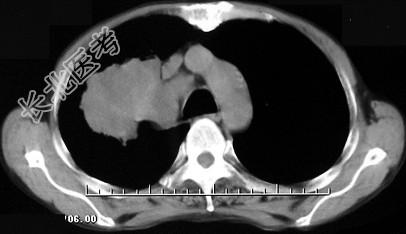

- 单项选择题男,68岁, 右侧胸痛伴右上臂麻木1周,胸部CT、MRI扫描如图, 最可能的诊断为 ( )

A、右上肺硬化性血管瘤

B、右上肺肉瘤并纵隔淋巴转移

C、右上肺不张

D、右上肺中央型肺癌并右上肺不张,纵隔淋巴转移

E、右上肺周围型肺癌并纵隔淋巴转移